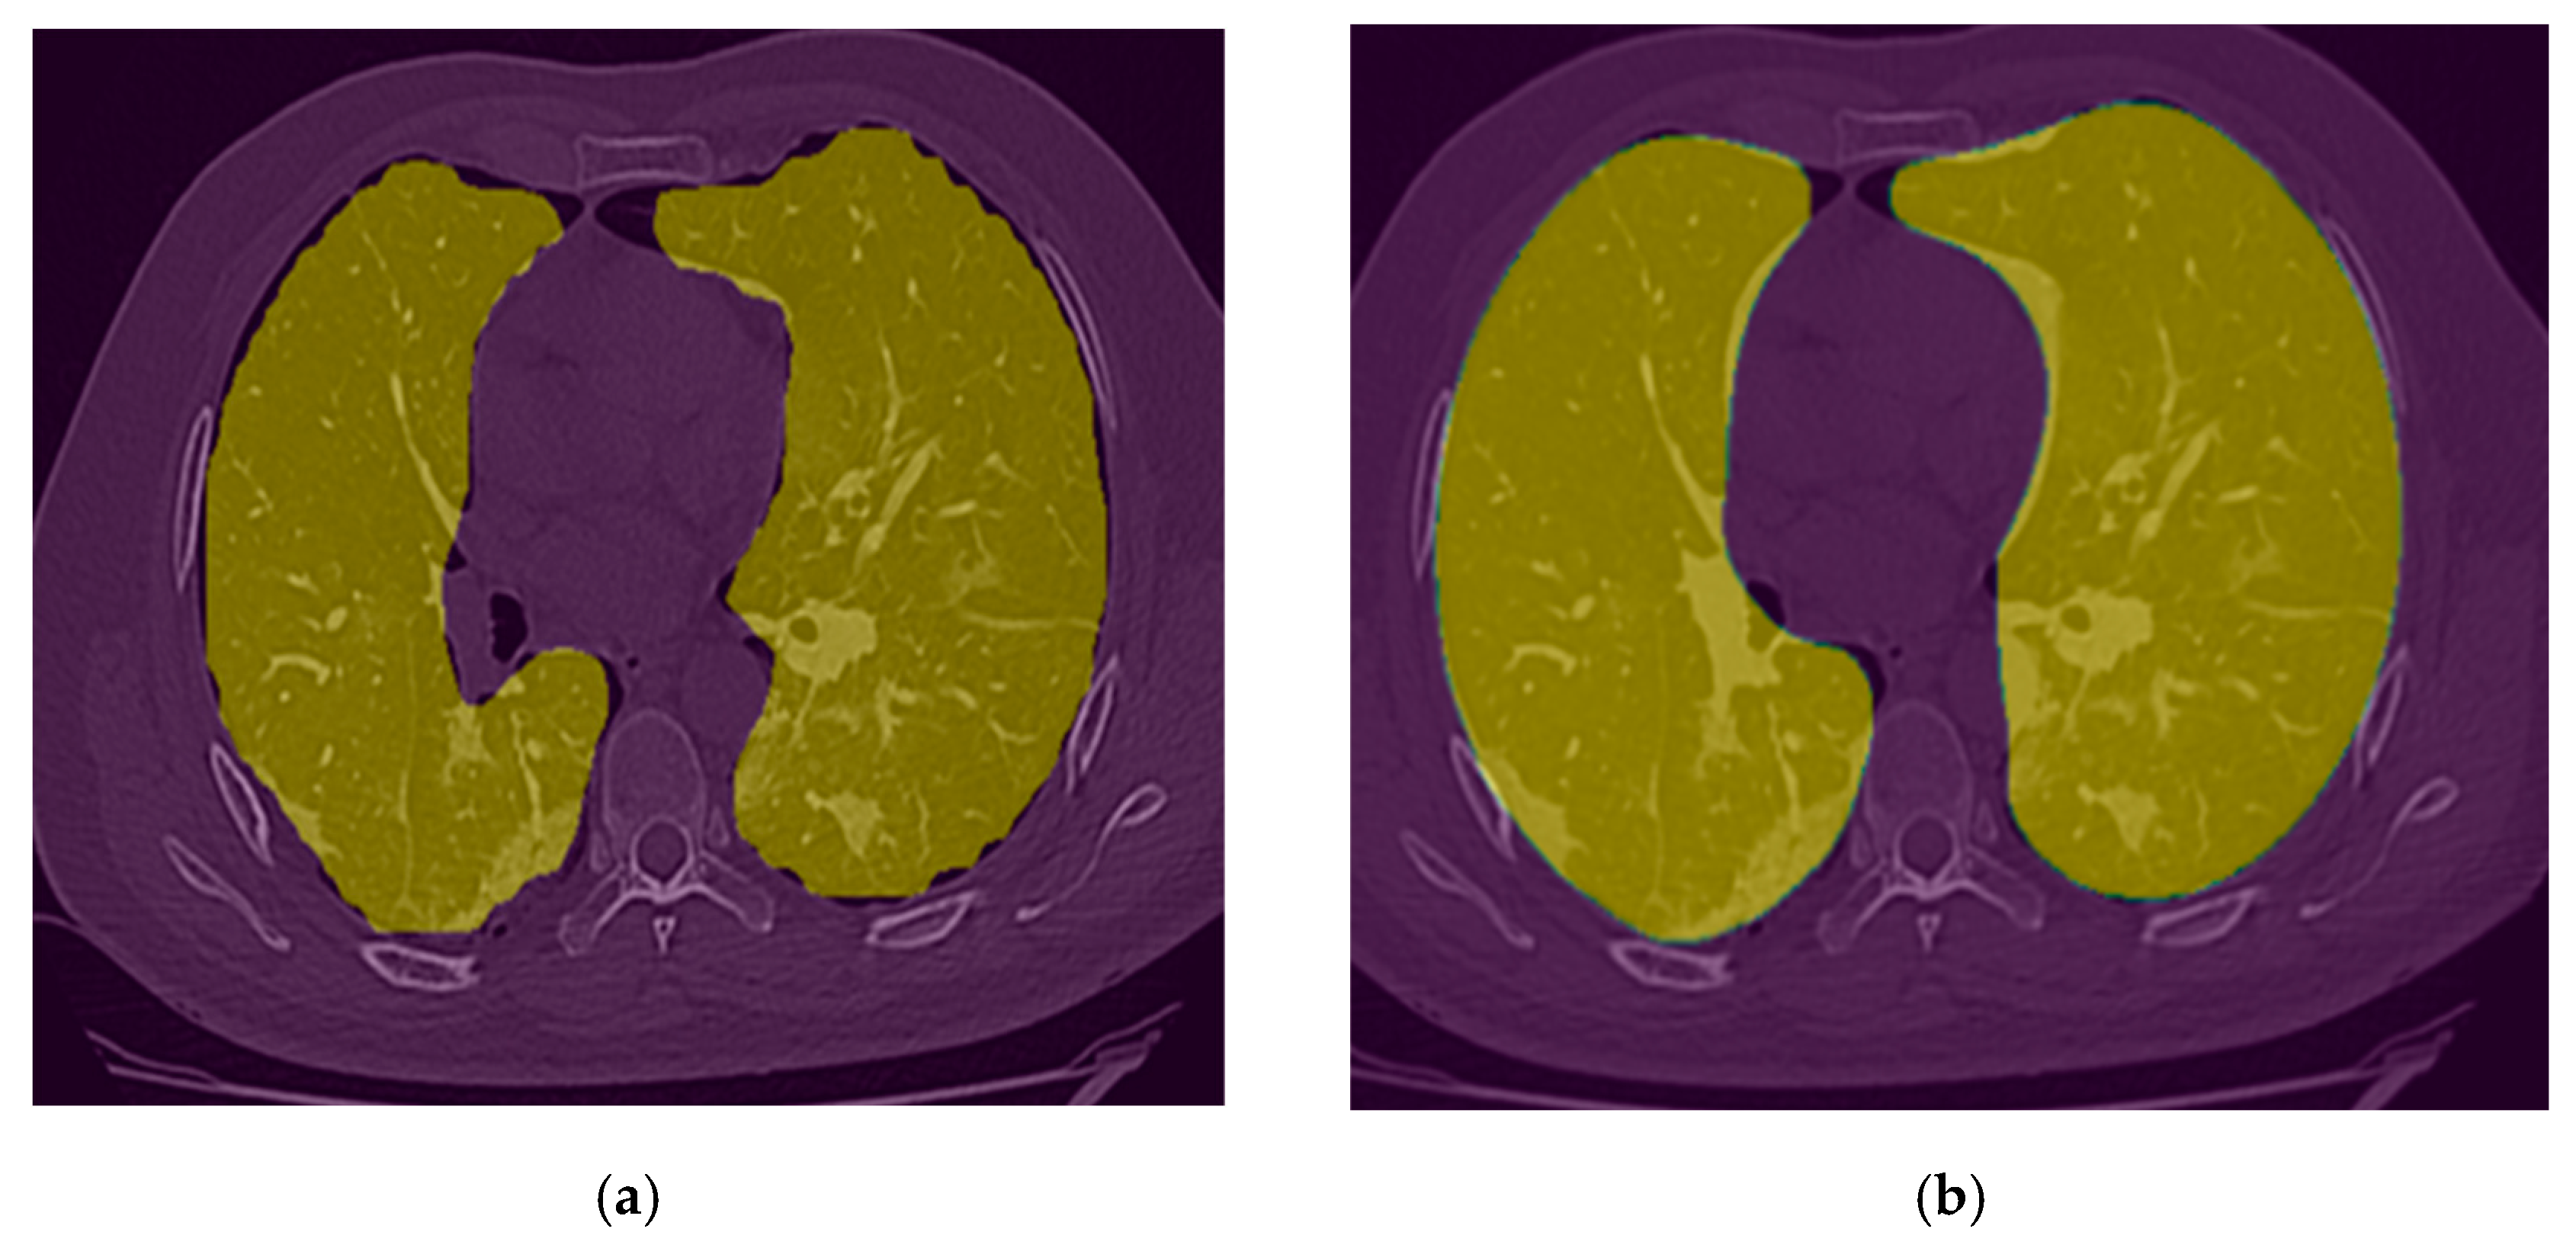

2.3.1. Lung Segmentation